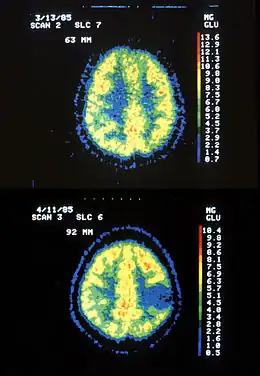

Deux images de PET Scan : en haut aspect normal, en bas une apparence d'astrocytome.

En début d'évolution, l'imagerie montre une tumeur isodense au scanner, d'où l'intérêt de l'IRM, plus sensible au dépistage de cette tumeur peu vascularisée. Lors de l'évolution, le scanner montre une tumeur hypodense, ne prenant généralement pas le produit de contraste. Il n'est pas retrouvé d'effet de masse puisque la tumeur est infiltrante.